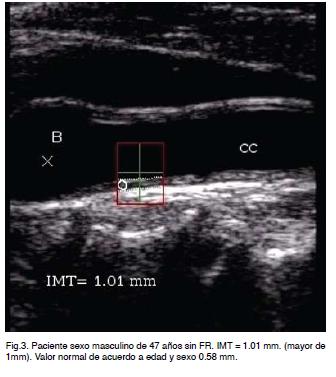

El incremento del espesor íntima-media es un indicador de enfermedad aterosclerótica. Para su evaluación se considera raza, edad y sexo. De acuerdo a diferentes estudios de grandes poblaciones se ha establecido la distribución de esta variable (espesor de íntima-media) según edad, sexo y raza tomándose el percentil como medida del porcentaje en que se divide la muestra.

Valores por encima del percentil 50 son considerados como positivos para el diagnóstico de aterosclerosis.

Valores por encima del percentil 75 indican riesgo CV aumentado (Figura 3).